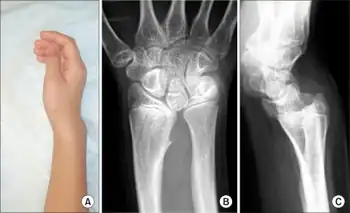

a) Appearance of wrist deformity b) AP view roentgenogram of wrist c) lateral view roentgenogram of wrist

Diagnosis is normally confirmed by X-rays.